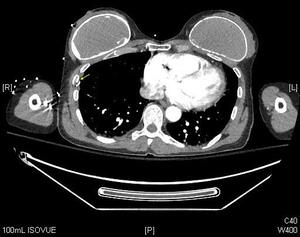

The CT scans of the abdomen and pelvis found no solid organ or hollow viscus injury. Spine CTs were negative for fracture or subluxation of the cervical, thoracic, or lumbar spine. Noncontrast brain CT was also negative for acute pathology. However, CT scans of the chest found right posterolateral third, fourth, fifth, sixth, seventh, eighth rib fractures [Figures 2,3]. A clavicle fracture was also found.